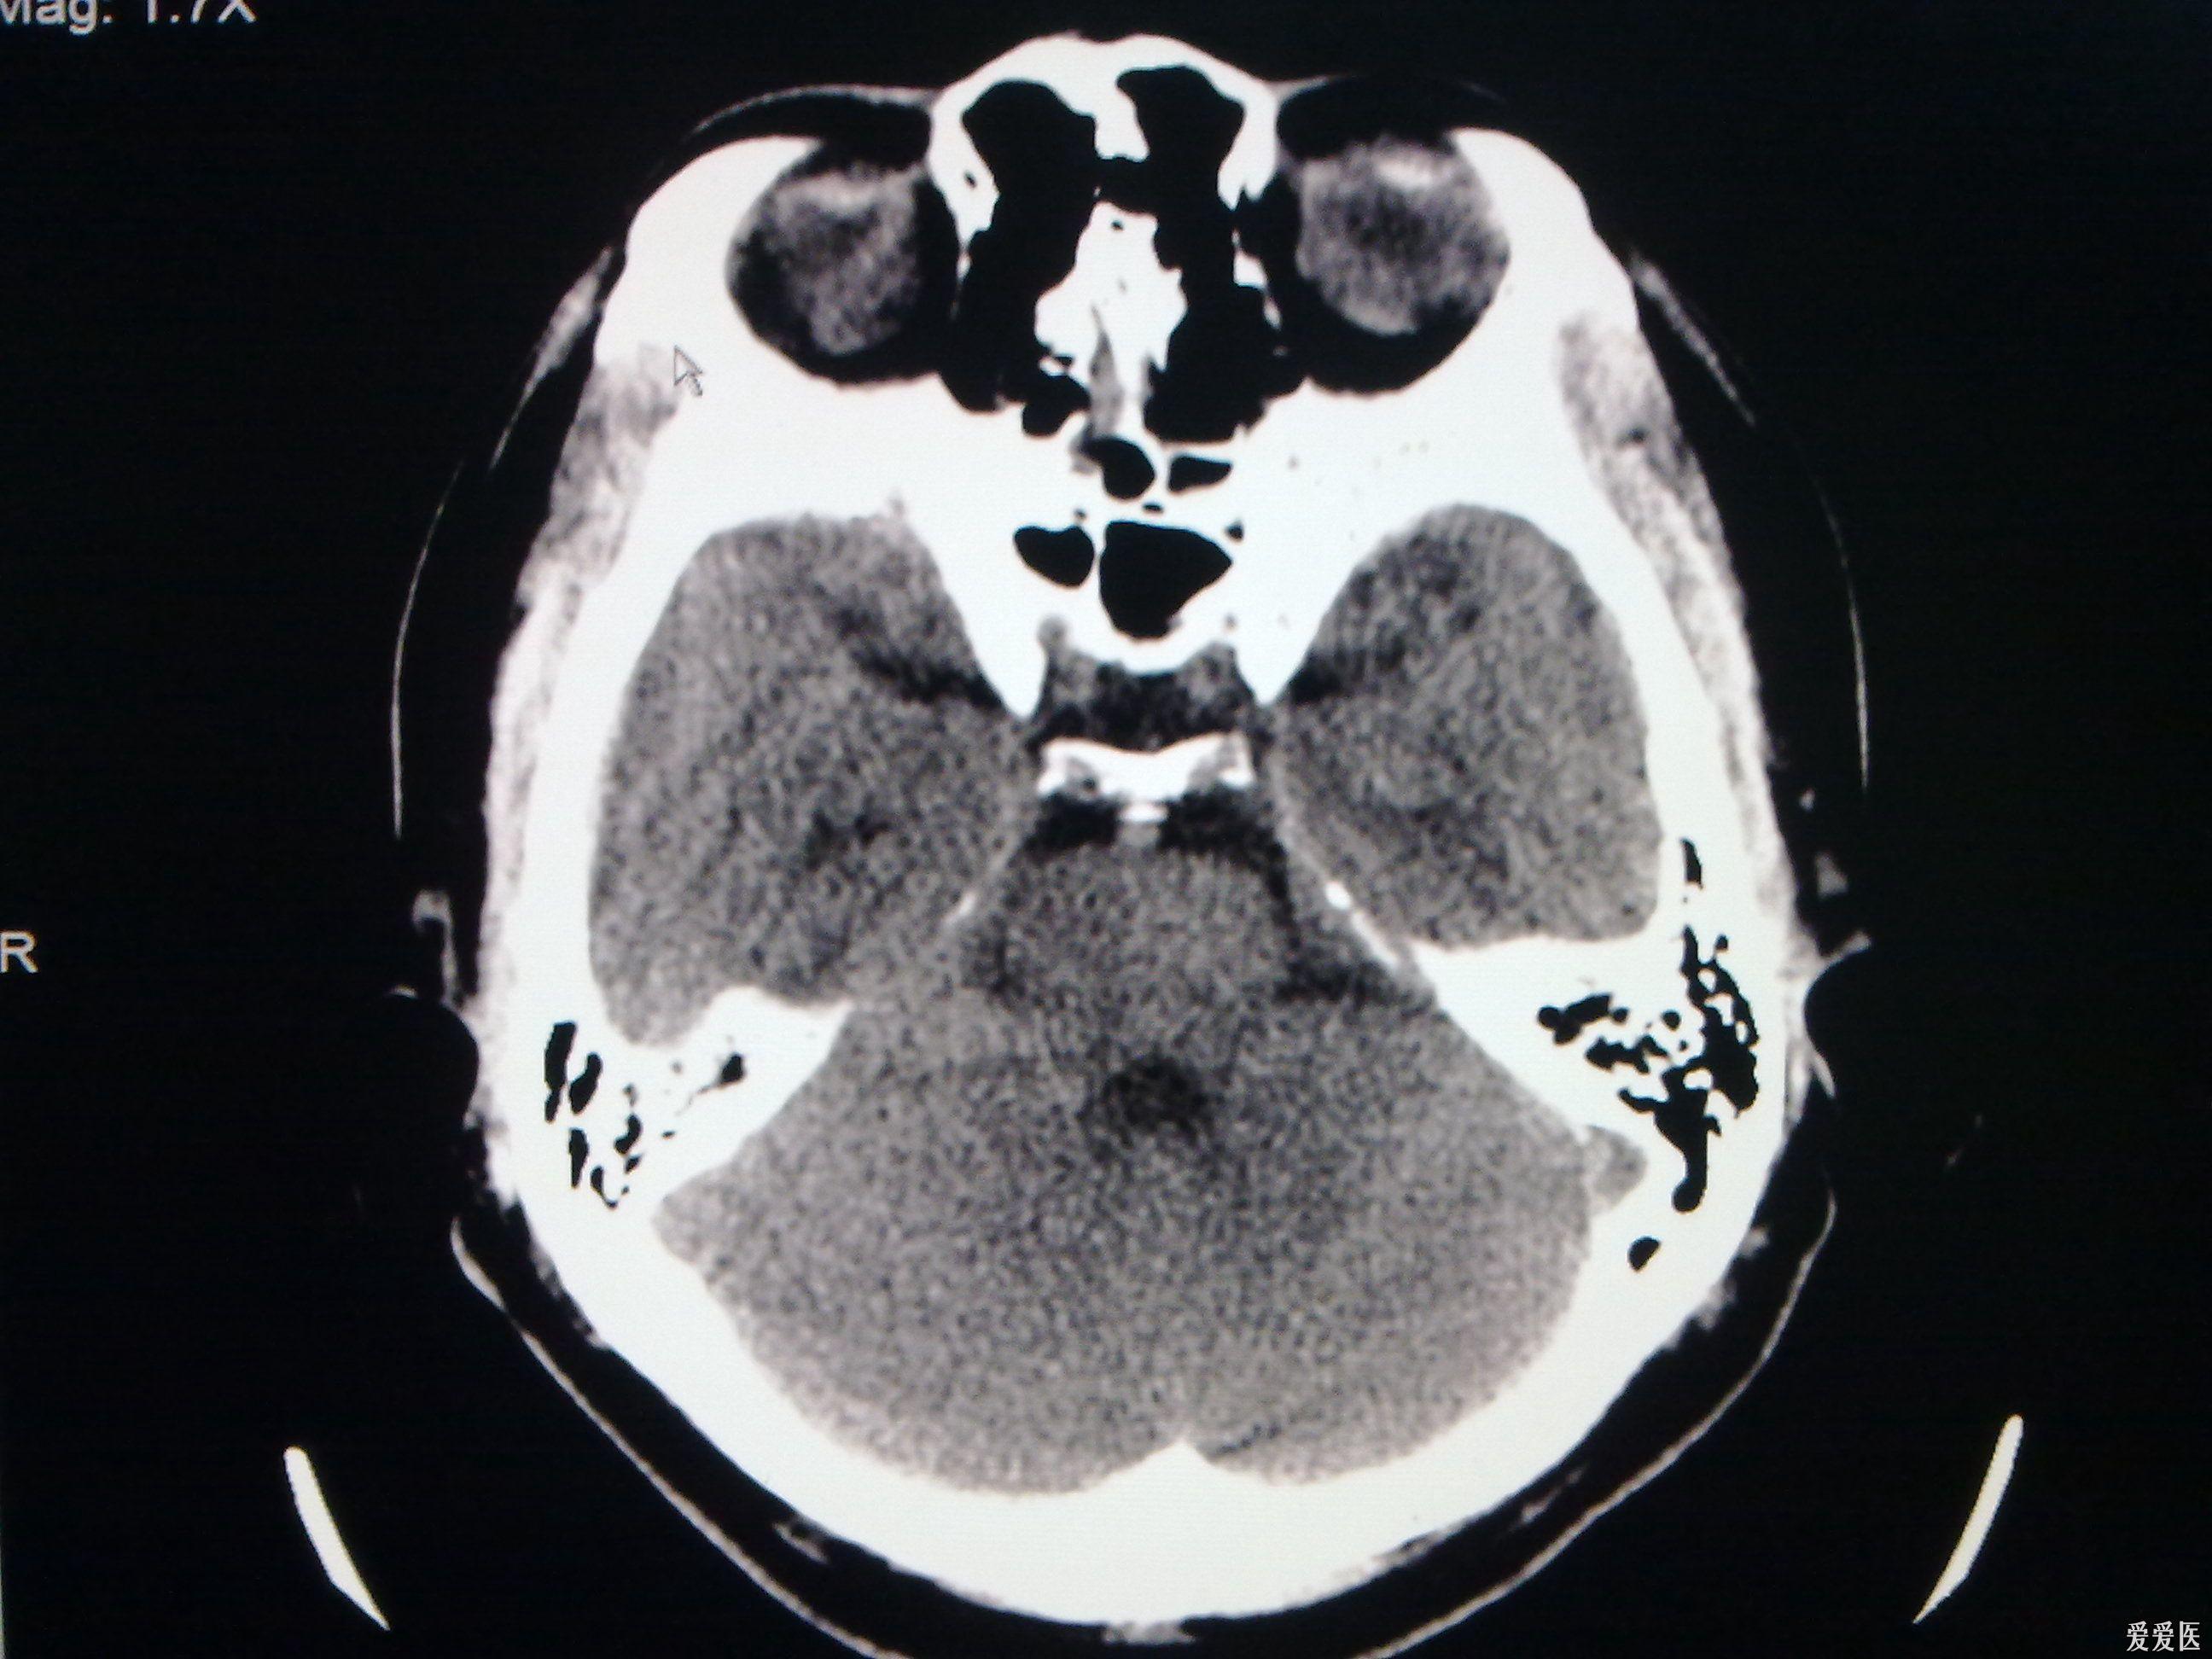

脑裂畸形ct表现

Ⅱ型脑裂畸形

今天做到的病例脑裂畸形

今天做到的病例脑裂畸形

今天做到的病例脑裂畸形

今天做到的病例脑裂畸形